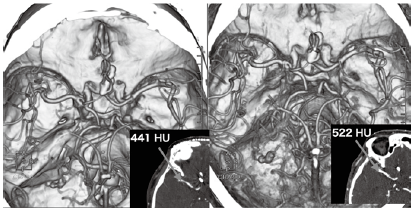

1つ目の症例は、頭部CT angiographyである。A-comの動脈瘤に対してクリッピング術がなされた経過観察の症例で156cm、52kgの女性である。Emotion16において1mmのスライス厚で画像を再構成できる条件で全脳撮影するには約15秒を要する。造影条件としては通常400mgI/kgを15秒注入し、生食を20mL後押ししている。この症例では、70mgI製剤を使用すると、56mLの造影剤が必要になる。この症例は、本番注入中に造影剤皮下漏れがあり、370mgI製剤80mLのうち残量が40mLとなってしまった。腎機能などを鑑みると、放射線科医からは残量で頭部CT angiographyを何とか実施して欲しいとのことであった。そこで、110kVから80kVに管電圧を下げ、造影効果の向上を図り、撮影範囲を限りなく短くし、pitch factorを上げて短時間撮影し、造影条件を4mL/s、40mLで検査を実施した。その結果を図3に示す。今回のイレギュラー撮影と通常撮影を比較し、中大脳動脈レベルにおいて血管内CT値は同等以上であり、診断上支障を来すことのない画像の提供に至った。